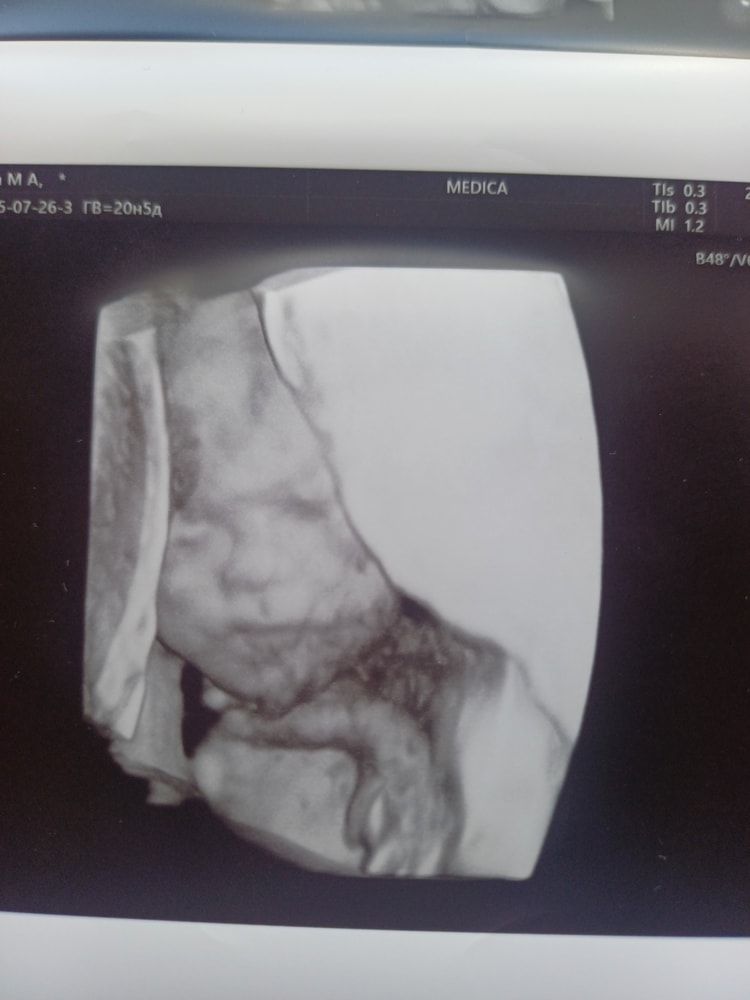

УЗИ, КТГ, доплерВчера ездили на второй скрининг.Всё отлично,человечек уже 374 гр.Всё узи держал пятки у лица,сидит на попе.(А я думаю чего так низко чувствую пиночки)Сначала совсем не хотел показываться,отвернулся к нам спиной. Узистка меня крутила и вертела по разному. Но потом дал полностью себя рассмотреть.И сестричкам помахал пяткой)Дочки с мужем зашли под конец узи посмотреть,они всю беременность мечтали именно в режиме реального времени увидеть малыша.🤩🤩🤩

Мы с мужем немного в шоке от информации,что у нас сын🥰Наш сынок,наш Александр Иванович.Но в очень приятном шоке.💕

С сыночком всё отлично,развивается по сроку.По месячным 20.2 недели,по узи уже 20.5.

Но единственное,что сильно меня огорчило,это короткая шейка,всего 28 мм😭Врач сказала пока не паниковать,через 2 недели сходить на кортрольное узи.А потом с результатами к своему гинекологу.Запишусь на 16 августа,как раз вернёмся из отпуска домой.